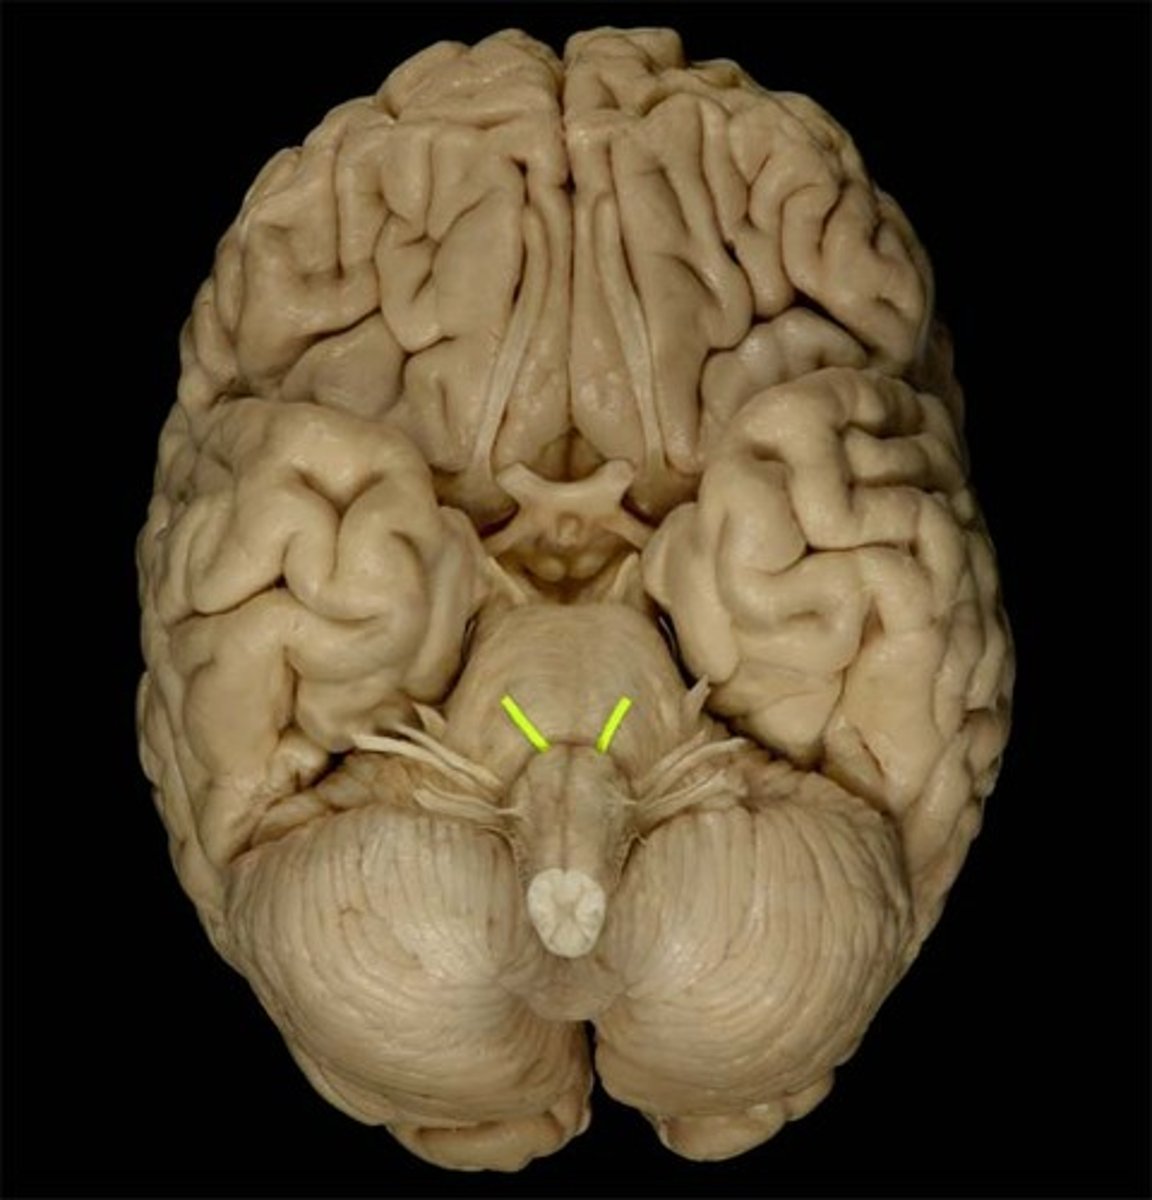

Trigeminal Nerve

Function: mixed (motor, general sensory)- mastication, touch, pain, temperature

Location: Pons

Abducens Nerve

Function: motor- eye movement

Location: Medulla-Pons junction